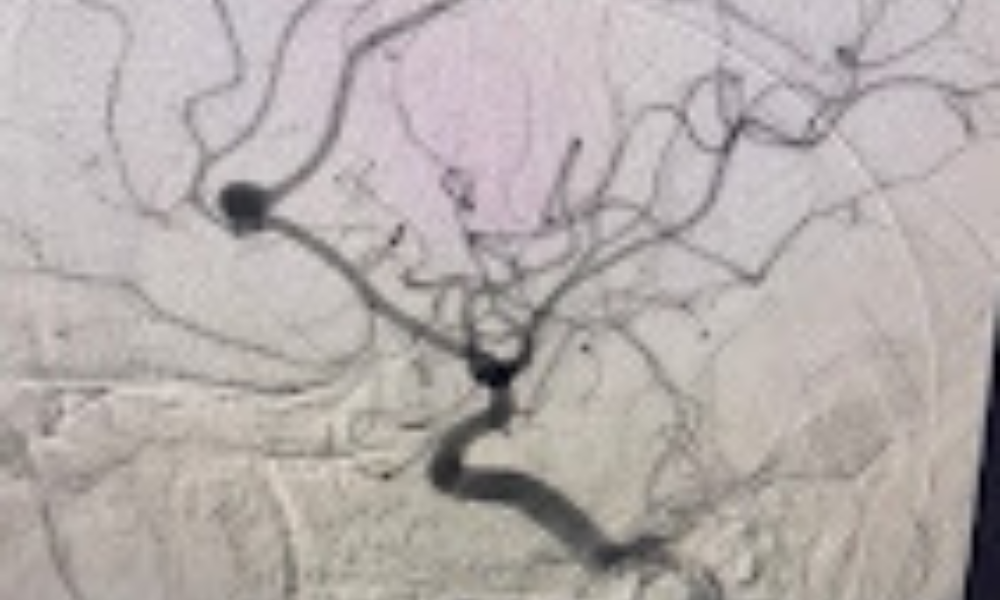

Aneurysm Clipping & Coiling Prevention of rupture with expert vascular neurosurgical techniques.

Brain & Neurosurgical Treatments